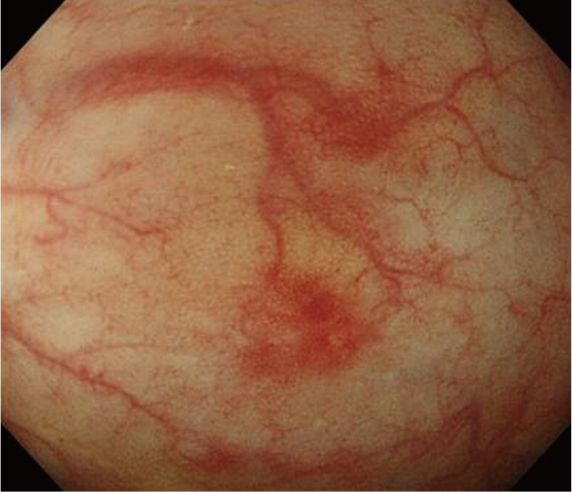

Рисунок 8. АА-амилоидоз у мужчины 55 лет с семейной средиземноморской лихорадкой. [3].

Очаговая гиперемия по ходу подслизистых вен. Гистопатологическое исследование подтвердило отложение амилоида.